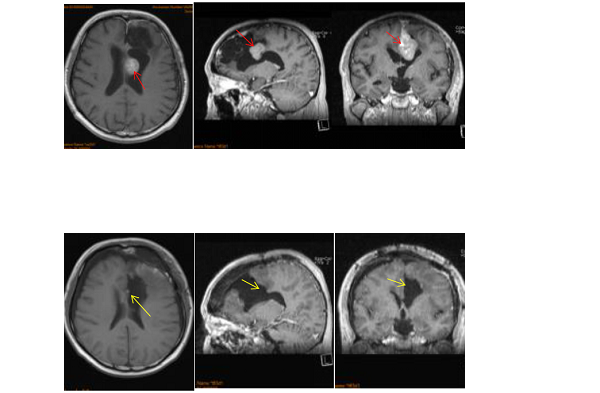

術(shù)前術(shù)后影像對(duì)比(矢狀竇旁腦膜瘤)